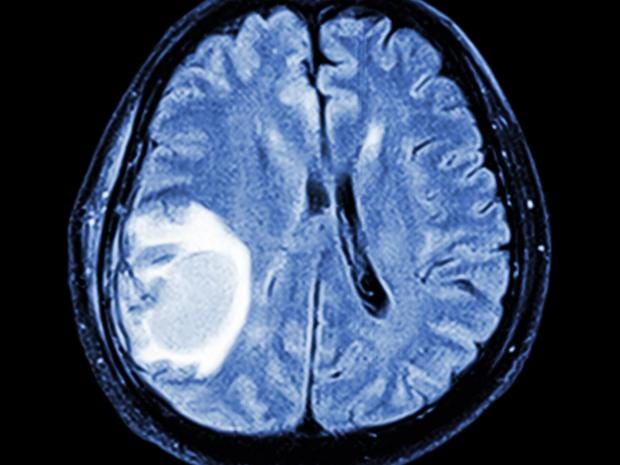

Brain tumours effectively treated by injecting patients with viruses

Aggressive brain tumours have been effectively treated by injecting viruses into patients.